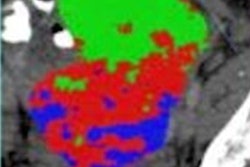

Since clinicians' performance reading contrast-enhanced CT images for assessing axillary lymph node metastasis can vary -- influenced as it is by their own experience and level of fatigue -- the investigators explored whether deep learning could aid in the task. They developed a deformable sampling module algorithm called deformable attention VGG19 (DA-VGG19) and used 800 contrast-enhanced CT images from 401 breast cancer patients to train, validate, and test the model; they assessed its accuracy, positive predictive value, negative predictive value, sensitivity, and specificity.